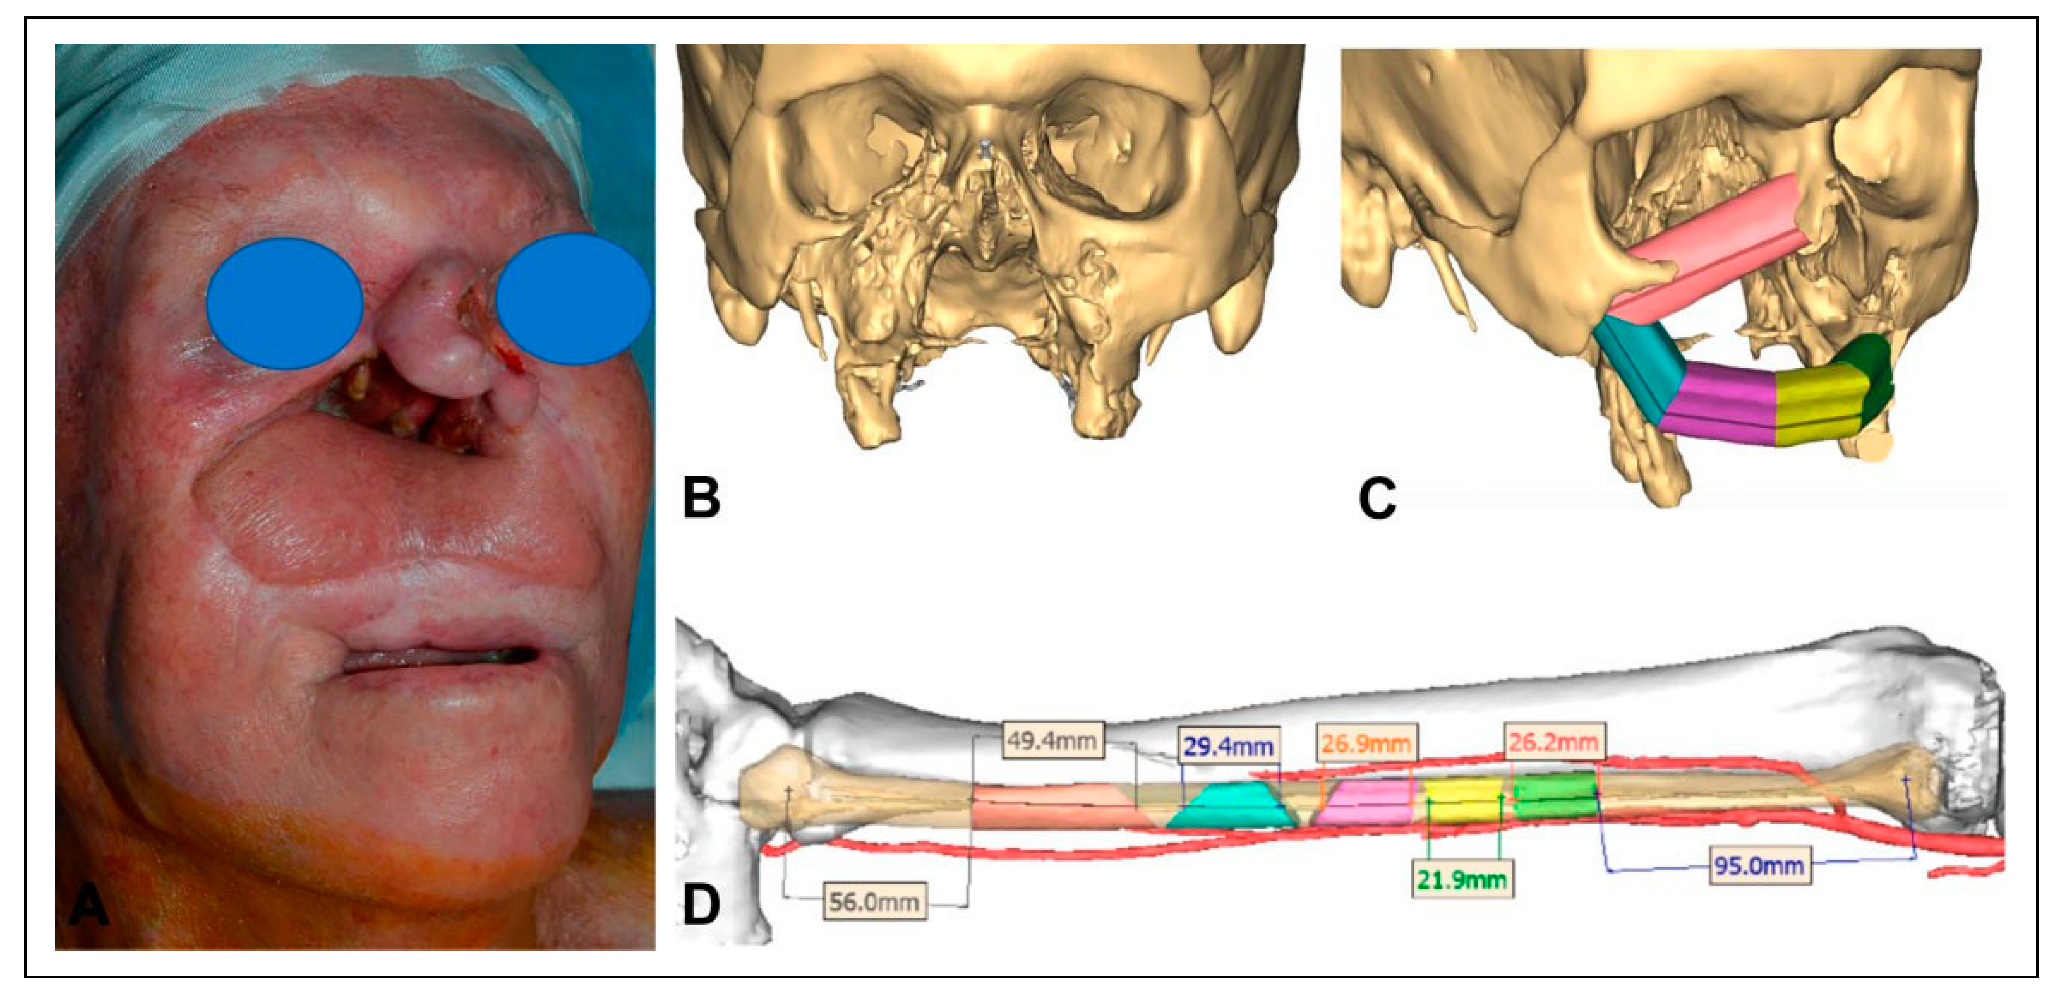

Figure 5. Frontal view of the patient status-post fibula free flap reconstruction of the mid-face (A). Panoramic radiographic of fibula reconstruction and implant rehabilitation with titanium framework (B). Surgical reconstruction to re-establish the stable base of the maxilla with an implant-supported fixed dental prosthesis provides optimal functional recovery to the patient.

The patient underwent reirradiation for orbital squamous cell carcinoma (SCC) with a second course of proton therapy (Figure 4). Despite the intervening radiation therapy, dental rehabilitation was successfully achieved with dental implants placed into the fibula flap (Figure 5).